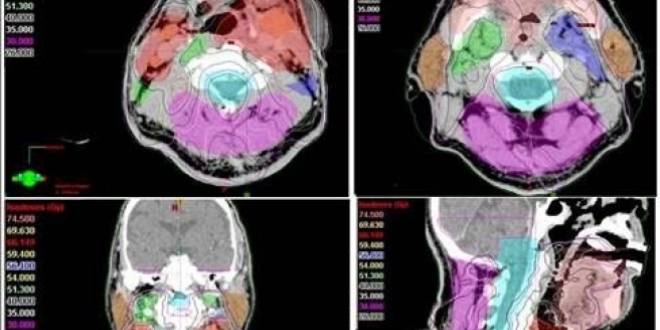

Antalya'da kanser kliniği uzmanlarından Radyasyon Onkolojisi Prof. Dr. Ali Aydın Yavuz, kanser hastalarının radyoterapisi sırasında 'Yapay Zeka' uygulamalarının kanserde tedavi başarısını arttırdığını belirtti. Son yıllarda yapay zeka uygulamalarının kanser alanında kullanılmasına yönelik araştırmalarda artış olduğunu ifade eden Prof. Dr. Yavuz, "Tümör ve çevredeki normal dokuların üç boyutlu olarak sınırlarının çizildiği bu süreç, bir hastanın tümör bölgesine ne kadar radyasyon alacağını ve ışının en uygun nasıl odaklanacağını belirler. Özellikle ABD'nin Ulusal Sağlık Enstitüsünce desteklenen önemli bir araştırma projesinde "Yapay Zeka' kullanarak yüksek riskli tümör hedef hacimlerinin sınırlarının 3 boyutlu olarak belirlenmesi için her bir görüntüleme film kesitinde tümör ve normal doku sınırlarının tek tek çizilmesi (konturlama) işlemlerini otomatikleştirmek için yeni bir yöntem geliştirildi" dedi.

Bu çalışmanın sadece yüksek riskli tümör hacimlerinin 'Yapay Zeka' ile otomatik bir şekilde ve çok yüksek doğrulukta belirlenmesine yönelik olduğunu dile getiren Prof. Dr. Yavuz, "Bir sonraki aşamada, eldeki tüm veriler birleştirilerek, orta ve düşük riskli tümör bölgelerinin de otomatik ve en doğru bir şekilde belirlenmesi mümkün olabileceği gibi, hastaya özgü en uygun radyoterapi veya kemoterapiyi de ayarlamak adına çeşitli genetik mutasyonlara ait bilgiler de bu yapay zeka uygulamasına entegre edilebilecektir. Bu şekilde, kanser tedavisi sonuçlarında başarı oranlarının artması da kaçınılmazdır. Yöntemin çok önemli bir avantajı da bizlere sunduğu yüksek hız ve verimliliktir. Normalde, örneğin bir baş boyun kanserinde, hedeflenen hacimleri belirlemek bir hekimin 1-4 saatini alır. Yapay Zeka kullanan özel bilgisayar sistemi ile hem bir dakikadan kısa bir sürede hedef hacimler belirlenebilmekte, hem de hekimden hekime değişebilen hata payları ihtimali tümüyle ortadan kalkmaktadır. Bu yöntem, özellikle, hedef hacim belirleme alanında tecrübeli uzman sayısının daha az olduğu düşük ve orta gelir düzeyindeki ülkelerde çok büyük bir kolaylık sağlayacaktır, ancak bu yöntemin ABD gibi gelişmiş ülkelerde de kanser tedavilerindeki yararlılık ve verimliliği çok artıracağı açıktır" şeklinde konuştu.